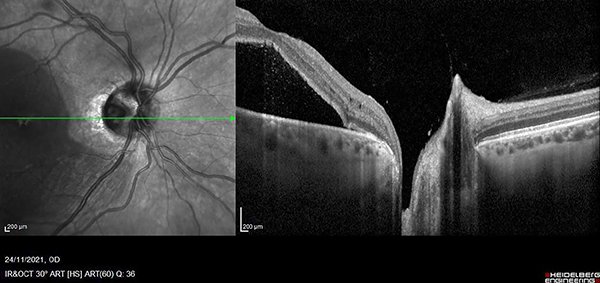

Paciente de sexo masculino de 47 años, sin antecedentes patológicos generales ni oculares de relevancia que consultó por guardia, derivado con diagnóstico de desprendimiento de retina en ojo derecho de un mes de evolución. Al ingreso presentaba una agudeza visual en ojo derecho (OD) de 5/10 sin corrección 10/10 con corrección (+1,50) y en ojo izquierdo (OI) 10/10 sin corrección. Test de Amsler alterado en OD. A la biomicroscopía ambos ojos se presentaban sin particularidades. Presión intraocular: 12/14 mmHg. Fondo de ojo derecho: papila bordes netos, excavada 0,7 atrofia peripapilar, pliegues maculares e impresionaba líquido subretinal; y en OI: papila bordes netos excavación 0,3, mácula de características normales, retina aplicada. Ante el diagnóstico presuntivo de coriorretinopatía central serosa (CCS) de OD solicitamos tomografía de coherencia óptica en donde observamos desprendimiento del neuroepitelio con compromiso de gran parte de la mácula (fig. 1). Pedimos ionograma sérico (no patológico) e iniciamos tratamiento vía oral con eplerenona 25 mg/día y tópico con bromfenac 1 gota cada 6 horas. A las dos semanas el paciente asistió a control sin mejoría de la visión (AV mejor corregida de 7/10) y sin cambios en el fondo de ojo. Realizamos nuevo OCT y vimos un aumento del líquido subretinal y retinosquisis parafoveal hacia nasal (fig. 2). Realizamos 3 inyecciones mensuales intravítreas de anti-VEGF (bevacizumab) y aumentamos la dosis de eplerenona a 50 mg/día durante 30 días, sin respuesta. A los tres meses, la AVMC era de 1/20, en el fondo de ojo, además de los pliegues maculares, observamos múltiples exudados duros maculares. Realizamos ecografía ocular a fin de descartar otras causas de desprendimiento seroso de retina y retinofluoresceinografía (RFG) en búsqueda de punto de fuga, sin hallazgos de interés (fig. 3).

Figura 1. OCT de ojo derecho con desprendimiento seroso del neuroepitelio.

Figura 2. OCT de control de ojo derecho con persistencia del desprendimiento seroso y retinosquisis.